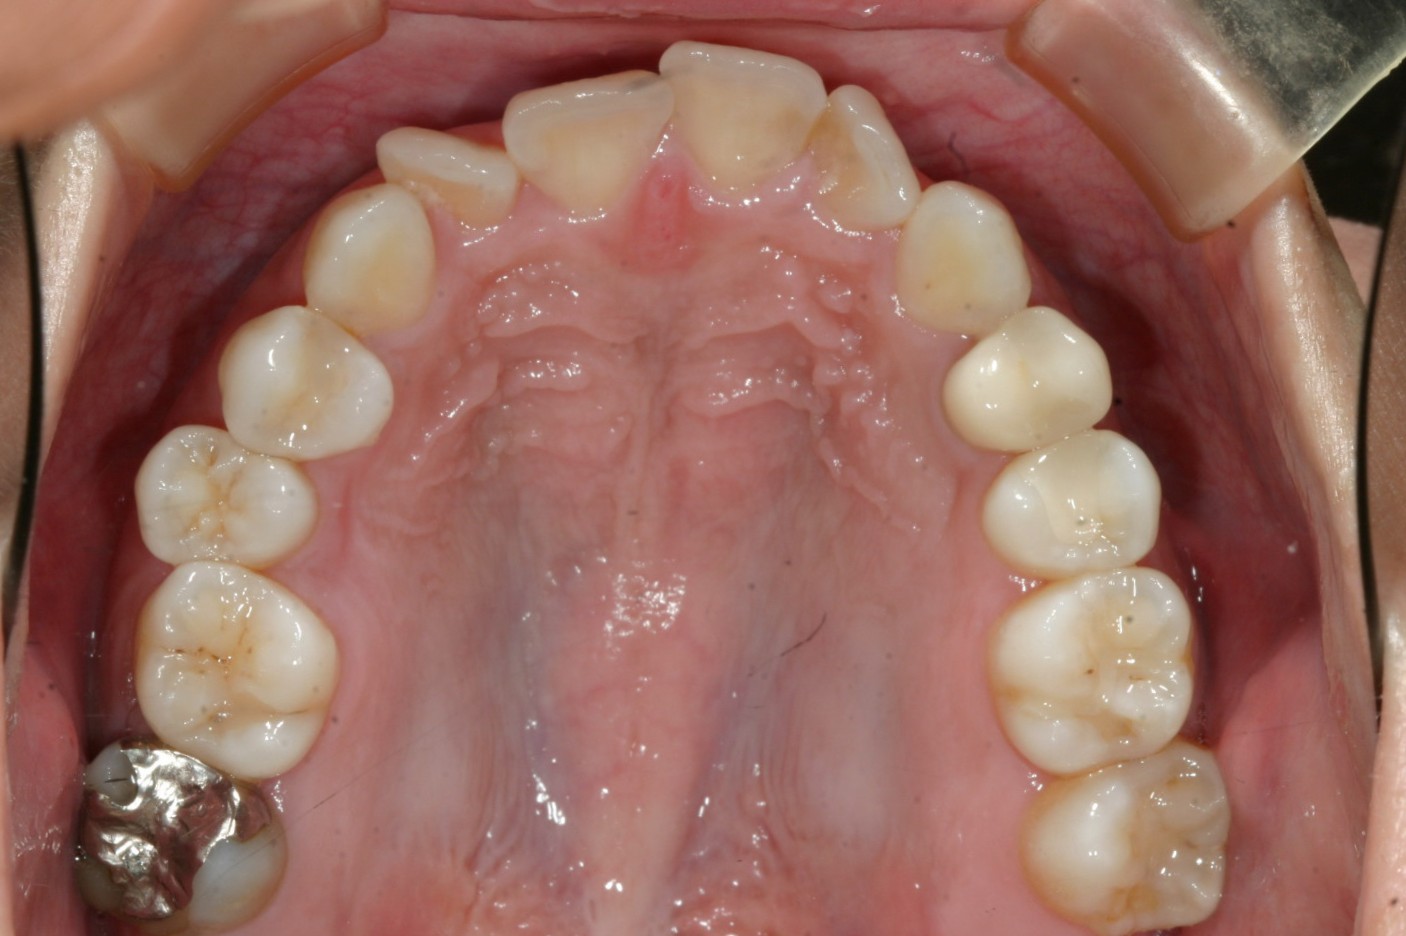

アーチが少し狭く前歯に叢生が見られます。 特に右側2番目の歯が捻転してますがこういった回転はインビザラインじゃ苦手な動きです。

アーチをU字に広げて前歯部の叢生を綺麗に取りました。